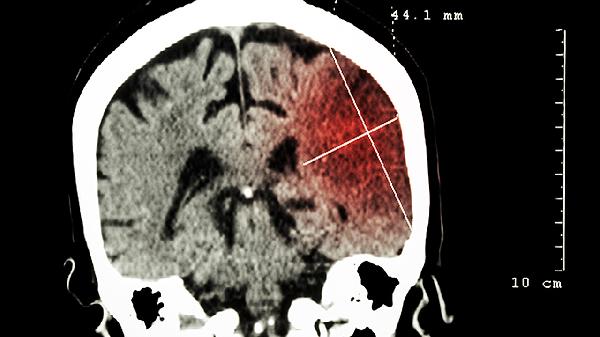

心脑舒通片中的有效成分能够改善脑部血液循环,缓解脑动脉硬化引起的头晕、头痛等症状。该药物通过扩张脑血管,增加脑血流量,帮助减轻脑组织缺血缺氧状态。脑动脉硬化患者使用时应定期监测血脂和血压水平,配合低脂饮食和适度运动。

4. 脑血栓形成后遗症

对于脑血栓后遗留的肢体功能障碍、语言障碍等后遗症,心脑舒通片可辅助改善脑部微循环,促进神经功能恢复。使用时需配合康复训练,定期复查凝血功能。老年患者应注意预防跌倒,家属需协助进行日常护理。